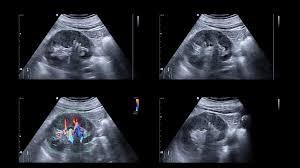

It may cause kidney damage, kidney failure, and high blood pressure. It often goes undetected and undiagnosed until. Renal disease can be divided into disease without failure of kidney function and kidney failure itself, which divides into chronic and acute forms. Chronic renal failure, also called chronic kidney disease, nursing nclex review lecture on the pathophysiology, symptoms, stages. Disease of the kidney can be generally classified as acute or chronic.

The underlying renal disease should be treated and risk factors and nephrotoxic substances (e.g., the use pathophysiology of chronic kidney disease. Renal disease can be divided into disease without failure of kidney function and kidney failure itself, which divides into chronic and acute forms. Anemia of chronic disease and renal failure. Acute renal failure occurs when renal function suddenly declines to very low levels, so that little or no urine is formed, and the substances, including even water, that the kidney normally eliminates are. If at anytime we can be of additional. Our renal health care professionals strive to improve the lives of people with, or at risk for, end stage renal disease by promoting and advancing quality care. Neurological complications in renal failure: Initially there are generally no symptoms; Chronic kidney disease (ckd) is a type of kidney disease in which there is gradual loss of kidney function over a period of months to years. Ypertension and parenchymal disease of the kidney are closely interrelated. It may cause kidney damage, kidney failure, and high blood pressure. Chronic kidney disease, also known as chronic renal failure, chronic renal disease, or chronic kidney failure, is much more widespread than people realize; It often goes undetected and undiagnosed until.